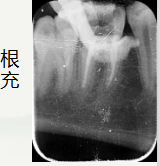

右下第一磨牙颌面大面积坏,可探及腔,叩+,无松动,无冷热刺激敏感。辅助检查:X线片显示左下第一磨牙远中邻面阴影,颌面阴影近腔,根尖口闭合,根尖无明显暗影。右下第一磨牙颌面大面积缺损,顶呈半散开状,根尖区闭合,伴根尖暗影。诊断:左下第一磨牙:急性牙髓炎

通过术前照与X线片,小牙片可见,颌面龋坏,远中邻面龋坏,叩+,松动-,

夜间自发痛,冷热刺激与对照牙对比反应明显。诊断为急性牙髓炎

开髓后